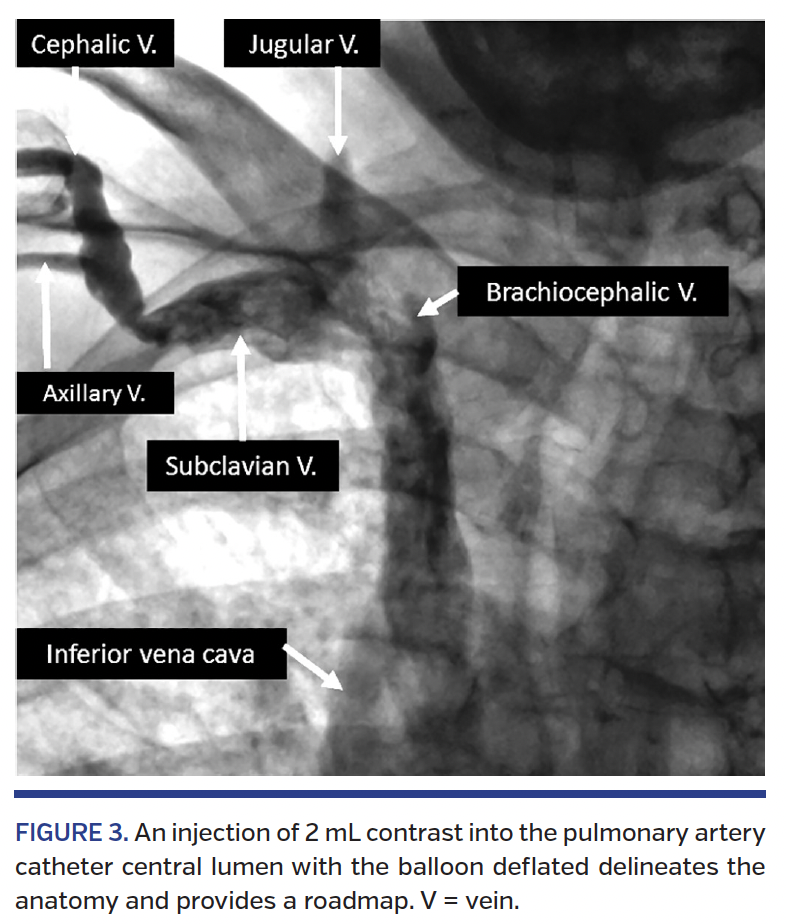

Catheterization. The initial 30-40 cm insertion of the PAC should be done without fluoroscopy while the balloon tip is deflated. There should be no resistance to the advancement of the PAC. If resistance is encountered, fluoroscopy with optional venography (to delineate a venous roadmap) is suggested. Within 30-40 cm, the PAC should reach the axillary and subclavian veins (Figure 2). At that point, advancing the catheter should be done under fluoroscopic guidance with the option of balloon inflation. Whenever there is any uncertainty about the patient anatomy, injection of contrast (via the major port of the PAC while the balloon is deflated) should be considered.

The advancement of the PAC is sometimes challenging, especially in older subjects harboring previous or current venous devices or leads in their venous system. Besides angiography that better defines the anatomy (Figure 3), one can use 0.014˝ or 0.018˝ soft-tip coronary or peripheral wires (170 cm length) to negotiate the tortuosity and challenging angulations of venous and cardiac structures. The typical tip of the wire should be prepared by the operator (our preferred starting angle is 45° at 1-2 cm from the distal tip of the wire. Typical friction point is the 90° entry point of the cephalic vein into the axillary vein and the right ventricular outflow track.